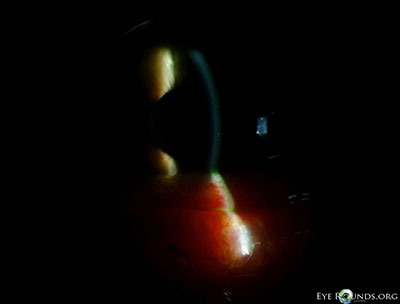

Figures 2-5: Slitlamp photographs demonstrating the conjunctivochalasis inferiorly

Figure 2 Figure 3

Figure 4 Figure 5